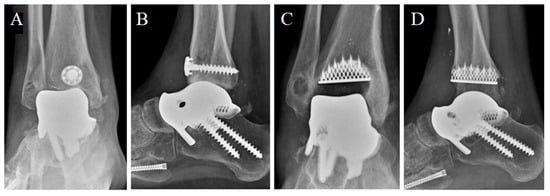

During the second year of follow-up, the patient experienced a worsening, up to the impossibility of walking without pain. He soon started complaining of painful plantar flexion and morning stiffness. A ROM limitation (ROM = 20°) was observed at the control visit. Two years after surgery, antero-posterior and latero-lateral ankle radiographs suggested a secondary osteoarthritis with articular space narrowing, implying the indication for a prosthesis revision (Figure 9). Either arthrodesis or tibial resurfacing were proposed as management options. In this case, the patient expressed the desire to maintain ankle function: A conversion to total ankle arthroplasty with TTR was performed. The tibial prosthesis consisted of a tibial trabecular titanium (Ti6Al4V) component and 6 mm-thick, high-density polyethylene (Figure 9). The lengthening of the Achilles tendon was performed using a percutaneous technique.

Figure 9.

Two-year post-surgery X-ray of the implant from antero-posterior (A) and latero-lateral (B) projections. Articular space narrowing and osteophyte formation (compared with Figure 7) can be observed (A,B). The total talar replacement after revision surgery from antero-posterior (C) and latero-lateral (D) projections. Image courtesy of Dr. Paola Verde Aerospace Medicine Department, Aerospace Test Division, Pratica di Mare, Rome, Italy.